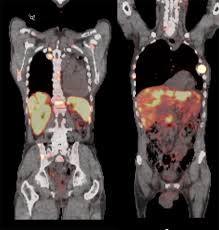

여기에 방사성 핵종 F-18를 붙여(F-18 FDG라고 함) 혈관 주사하면 빨리 자리는 암세포는 포도당이 더 필요해 정상 세포보다 10∼100배 더 많이 모여들고 이를 방사능으로 촬영해 찾아낸다. 암이 1㎝만 돼도 10조개의 암세포가 있어 CT, MRI 소견이 애매한 경우 유용하게 쓰인다.

PET의 또 다른 장점으로 거의 모든 종류의 암을 찾아낼 수 있다는 것이라고 한다. 일반적으로 암세포는 포도당 대사가 높기 때문이라고 한다.

또 머리끝에서 발끝까지 촬영해 어느 곳에 있는 암이라도 잡아낸다. 다시 말하면 사각지대가 없다고나 할까? 이미 일본에서는 이 방법으로 암을 검진하는 프로젝트를 성황리에 진행하고 있다고 한다.

그러나 일본의 경우 증상이 없는 PET 검진자의 1∼2%에서 암을 찾아내고 있다고 한다. 또 이미 암을 진단받은 후에도 전신 PET를 해 보면 5∼7%에서 숨어 있는 다른 암을 찾을 수 있다고 한다.